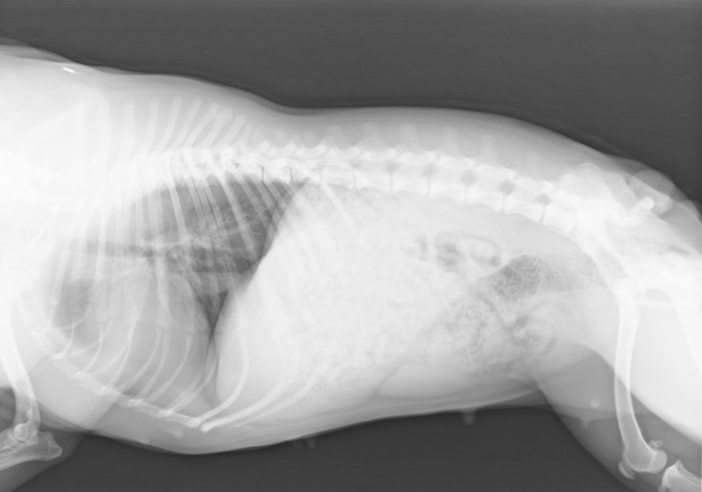

HD (Hüftgelenksdisplasie) & ED (Ellenbogengelenksdisplasie)

Die Anzeichen einer HD variieren abhängig von Alter des Hundes und dem Stadium der Krankheit. Junge Hunde beispielsweise haben Schmerzen, weil der Oberschenkelkopf nur ungenügenden Halt in der Hüftgelenkspfanne findet und dadurch die Nervenfasern der Knochenhaut gereizt werden. Bei älteren Tieren treten Schmerzen aufgrund von Arthrosen des Hüftgelenks auf.

Zunehmende Beschwerden bei Spaziergängen sind die Folge. Der Hund möchte nicht mehr weit laufen, setzt sich öfter hin, zeigt einen instabilen Gang, lahmt häufiger und jault beim Spielen gelegentlich auf. Meist lassen die Hunde sich beim Hinlegen einfach fallen und auch Knirsch- oder Knackgeräusche des Gelenks können hörbar sein.